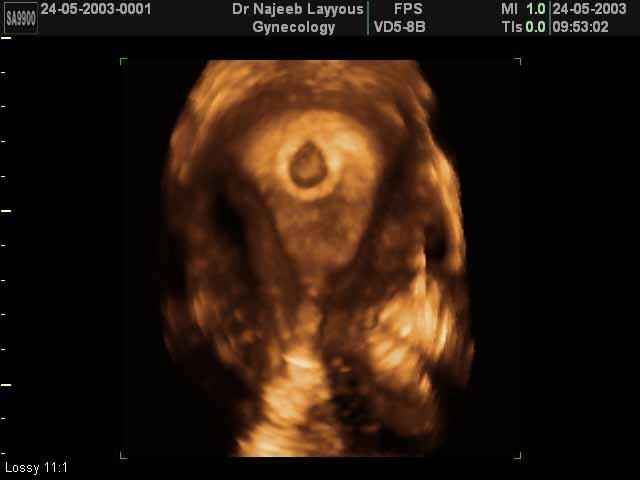

- 3D Photos Ecographie du Premier Trimestre